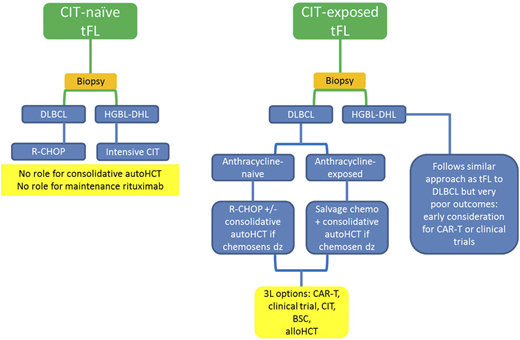

The best initial treatment depends on the prior therapy for the underlying indolent lymphoma and the histology at the time of transformation (Figure 3). There are several clinical scenarios to consider: tFL in treatment-naïve patients with FL (including simultaneous diagnosis of FL/tFL), tFL after prior anthracycline-based chemoimmunotherapy, and tFL developing after prior therapy that did not include cytotoxic chemotherapy. An example of a scenario with almost no data is when HT occurs after prior bendamustine-based chemoimmunotherapy and whether to treat these patients similarly to anthracycline-exposed patients is unclear.

Graphic summary of how I treat tFL. CIT, chemoimmunotherapy; BSC, best supportive care; HCT, hematopoietic stem cell transplant.

Graphic summary of how I treat tFL. CIT, chemoimmunotherapy; BSC, best supportive care; HCT, hematopoietic stem cell transplant.